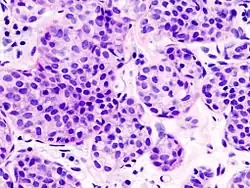

| Alveolar | 5% | Aggregates of classical-appearing cells | |

| Pleomorphic | Classical-appearing but with pleomorphic cells. It may include signet-ring cells, or plasmacytoid cells (pictured) which have abundant cytoplasm and eccentric nuclei. | ![]() |

Histopathology of invasive lobular carcinoma (ILC), next to lobular carcinoma in situ (LCIS) -

Invasive lobular carcinoma demonstrating a predominantly lobular growth pattern -

Lobular breast cancer. Single file cells and cell nests. -

ILC may be subtle on low magnification (left). Higher magnification (right) shows invasive growth pattern and vesicular nuclei with prominent nucleoli.